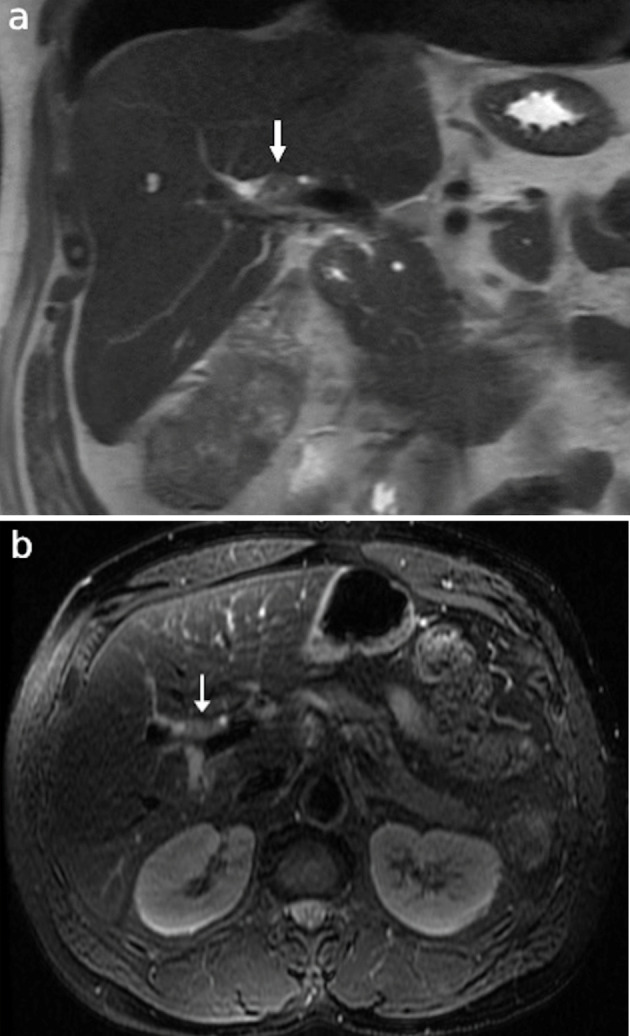

在极少数情况下,恶性胆道梗阻可能源于远处原发肿瘤转移到胆管。由于胆管转移瘤在临床和影像学上可能与胆管癌等原发性胆道肿瘤相似,因此这种现象往往给诊断带来挑战。我们介绍了一例独特的结直肠腺癌患者单发同步导管内胆管转移导致胆道梗阻的病例。患者最初被新诊断为肝曲处结肠癌,横断面影像学检查发现导管内肿块导致胆道梗阻。最初,导管内病变的性质并不确定,但通过组织病理学检查,最终确诊为转移性结直肠腺癌。该病例强调了区分转移性胆道梗阻和原发性胆道肿瘤的难度,并突出了在胆道肿块的非典型表现中考虑转移性疾病的重要性。我们讨论了有助于区分导管内结直肠腺癌转移瘤和原发性胆道肿瘤的几个关键放射学和组织病理学特征。

Malignant biliary obstruction can, in rare cases, arise from metastases to the biliary tree from distant primary tumors. This phenomenon often poses a diagnostic challenge, as bile duct metastases may clinically and radiologically mimic primary biliary tumors, such as cholangiocarcinoma. We present a unique case of solitary, synchronous intraductal biliary metastasis in a patient with colorectal adenocarcinoma that led to biliary obstruction. The patient initially presented with a new diagnosis of colon cancer at the hepatic flexure and was found, on cross-sectional imaging, to have biliary obstruction due to an intraductal mass. Initially, the nature of the intraductal lesion was uncertain; however, it was ultimately confirmed through histopathological examination to be metastatic colorectal adenocarcinoma. This case underscores the difficulty of distinguishing metastatic biliary obstruction from primary biliary tumors and highlights the importance of considering metastatic disease in atypical presentations of biliary masses. We discuss several key radiologic and histopathological features that may help differentiate intraductal colorectal adenocarcinoma metastases from primary biliary tumors.